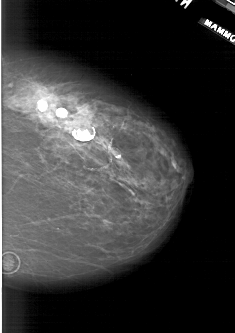

A_1941_1.RIGHT_MLO

RIGHT_MLO LINES 6271 PIXELS_PER_LINE 3811 BITS_PER_PIXEL 12 RESOLUTION 43.5 NON_OVERLAY